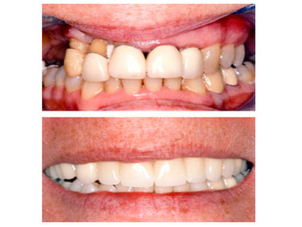

Foto de Odontología Integral y Estética, Dr Fernando Andrade Drpic

Al momento de elegir al especialista que tratará alguna de las patologías relacionadas con la Periodoncia, el paciente debe tener en cuenta varios factores. Según explican desde la Sociedad de Periodoncia de Chile, para que un médico pueda ser socio este debe contar con el título profesional de Odontología y con algún Magíster o grado académico superior en Periodoncia otorgado por una universidad chilena o extranjera acreditada o reconocida en Chile o por la Corporación Nacional Autónoma de Certificación de Especialidades Odontológicas.

Así mismo y con la finalidad de contar con diversas opiniones sobre el caso y tratamiento a seguir, es recomendable que el paciente visite diversos especialistas en ortodoncia para revisar opiniones, puntos de vista y pueda investigar sobre los casos de éxito en situaciones similares.